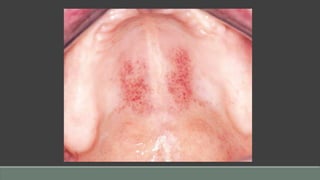

Petechiae

Definition: Petechiae are pinpoint hemorrhages that occur in subcutaneous or submucosal

tissues in a wide variety of conditions. Because of their diversity, the differential diagnosis of

oral mucosal petechial hemorrhages is complex.

Etiology

• Viral infection (Epstein-Barr virus [EBV]-mononucleosis; measles), rickettsial infection

• Thrombocytopenia, leukemia

• Disseminated intravascular coagulation (DIC)

• Trauma: prolonged coughing, frequent vomiting, giving birth, violent Valsalva maneuvers

Clinical Presentation

• Pinpoint hemorrhage into mucosa/submucosa

• Asymptomatic

• Usually involves the soft palate

• No blanching on pressure (diascopy)

Diagnosis

• Clinical features

• History, determination of underlying cause

Differential Diagnosis

• See “Etiology”

Prognosis

• Variable, depending upon etiology

• Does not require treatment; observation only